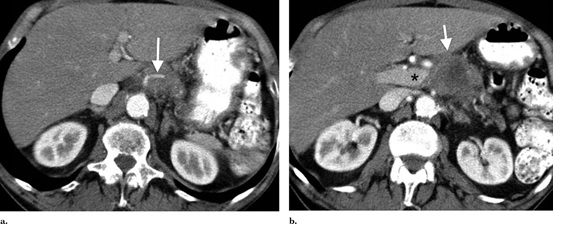

一名76歲的非裔美國(guó)男性診斷出患有不可切除胰腺癌III期(腫瘤/瘤/轉(zhuǎn)移階段)在他拒絕了化療和射頻之后二次血管入侵使得他選擇了經(jīng)皮IRE(納米刀消融術(shù))技術(shù)。CT成像(圖表 1)表明4.1X4.1X3,5cm腫瘤包含腹腔動(dòng)脈,腸系膜上靜脈的起源,肝外門靜脈堵塞和上腸系膜靜脈。全身CT掃描顯示沒有轉(zhuǎn)移性疾病。

圖一:腫塊大?。?.1X4.1X3,5cm,腫瘤侵犯了腹腔動(dòng)脈、腸系膜上靜脈、肝外門靜脈